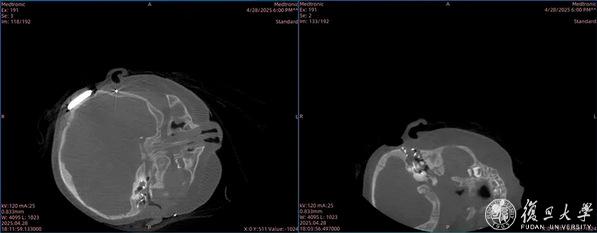

术中“O”臂机成像后判断双耳耳蜗电极位置符合预期